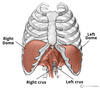

What is this muscle?

Rhomboid major